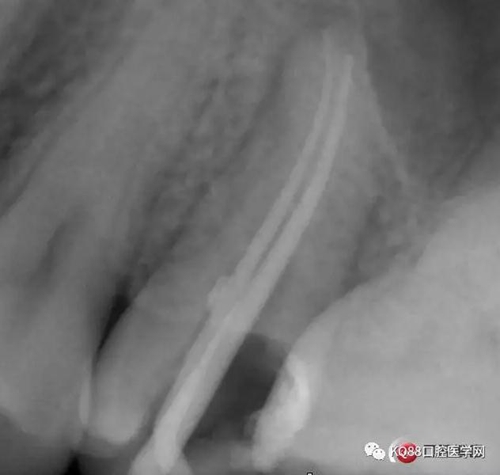

當我第一次完成操作后,再次拍了一個插針片,發(fā)現(xiàn),距離根尖孔有1.5mm,書上說的是2mm安全區(qū),可能如果隨意點,就直接充填了,我想說明的是,我們做根管,千萬不要馬虎,不要湊合,一定嚴謹?shù)膽B(tài)度,于是我重新再回到C銼,再開始耐心的預備,完成之后,再拍攝了插針片。

此次明顯可以看見根尖分開了兩個根尖孔,根管治療永遠就只是那一點,如果都只是隨便做一下,我相信,沒有復雜的牙齒,根管治療都會很簡單,態(tài)度決定一切,我不敢說我做的會很好,但是我會靜下心來,慢慢操作,這樣才能做得對的起自己和患者。于是根充完成,再次拍攝。